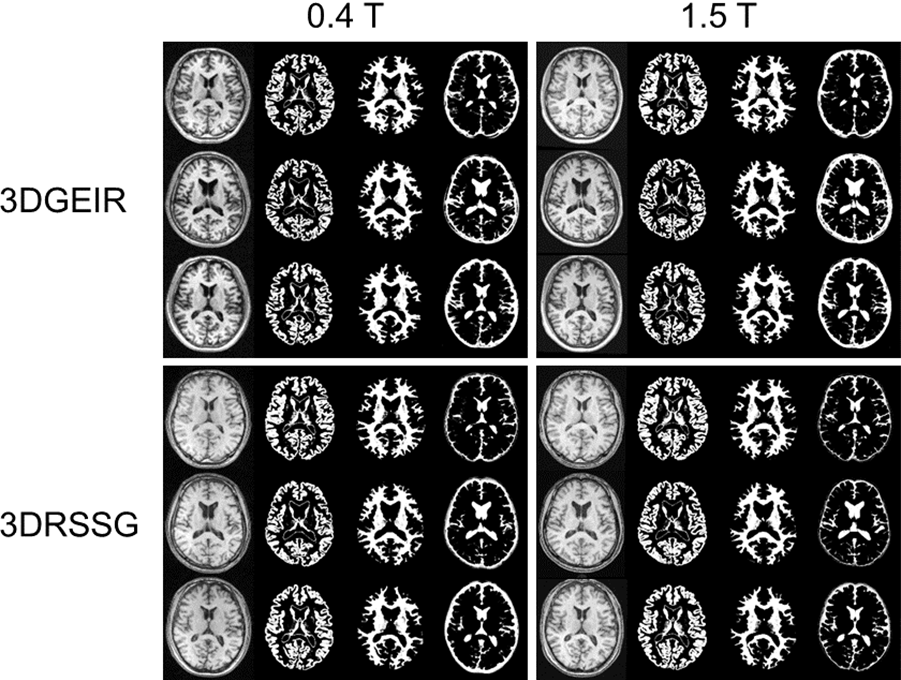

この最適化した撮像シーケンス・パラメータを使用し、同一ボランティアで0.4テスラ装置(APERTO Lucent*1)と1.5テスラ装置(ECHELON OVAL*2)で3D T1強調画像を撮像した例を図1に示す。VBMで一般的に用いられる組織自動分離抽出結果を利用して灰白質・白質・脳脊髄液の信号コントラストを算出すると、3DGEIRでは0.4テスラのボランティア3例の平均で白質・灰白質コントラストが1.63、脳脊髄液・灰白質コントラストが0.33となり、小数例での検討ではあるが1.5テスラの1.39と0.39と比較してむしろ高いコントラストを有することが示された。3DRSSGでは0.4テスラで白質・灰白質コントラストが1.35、脳脊髄液・灰白質コントラストが0.55となり、1.5テスラの同シーケンスではそれぞれ1.29と0.50であったため、ほぼ同等のコントラストが得られていることが確認できた。

図1 同一ボランティアにおける0.4テスラ装置と1.5テスラ装置による3D T1強調画像(上段:3DGEIR、下段:3DRSSG)

次にVSRADによるセグメンテーションの結果を図2に示す。0.4テスラ装置においても1.5テスラ同様に良好な組織分離抽出結果が得られていることが確認された。萎縮部位を確認すると、広さと強さに若干の差があるものの類似した萎縮パターンが描写されていることが分かる(図3)。またVSRADの主たる結果指標であるVOI内萎縮度のzスコアも、0.4テスラと1.5テスラの差が3DGEIRで0.33±0.20、3DRSSGで0.22±0.13と近い値が得られていることが確認できた。

図2 0.4テスラ装置と1.5テスラ装置による3D T1強調画像のVSRADによるセグメンテーション例(上段:3DGEIR、下段:3DRSSG)